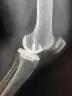

近年来,微创、保膝的理念逐渐被大家所接受。微创单髁置换手术就是微创保膝理念的有效解决办法之一。它也叫做部分膝关节置换术,手术只是将膝关节内侧部分磨坏的股骨和胫骨骨头切除,装上非常耐磨的人工材料,保留外侧未磨损的关节和关节内所有韧带。而且手术可以通过比全膝置换小得多的伤口来完成,其创伤小、出血少、恢复快、假体寿命长、功能恢复程度高等一系列优点正逐步的显示在世人眼前。

微创单髁置换小切口(上)

微创单髁置换小切口